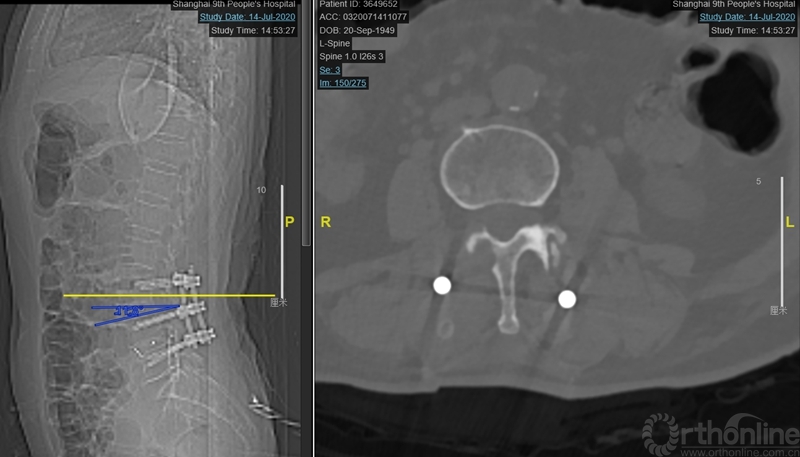

本文提供一例病例,高PI的腰椎显著前凸多节段的腰椎管狭窄症合并腰椎滑脱的患者(PI:57度,LL: 62度,图1、2、3),术前影像显示腰3-4、4-5椎管狭窄、椎体滑脱(图2、3),术前临床表现为右侧下肢麻木无力症状,术中接受了双节段MIS-TLIF手术。

图2:术前腰椎正侧位:腰3-4、4-5滑脱。腰椎矢状面顶椎腰23椎间隙,LL:62°,L34椎间隙与水平成角度21°,L45椎间隙与水平成角26°,椎间隙方向为术中工作通道方向。

图4:第一次术后X ray